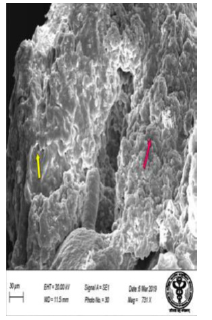

The scanning electron microscopic examination of duodenum in control rat revealed goblet cells distended with mucus in between the enterocytes (Figure 25). The epithelial cells with long and short microvilli were present (Figure 26). The rats treated with 600 mg NaF/kg b.w./day for 40 days, revealed apparent erosions and fissures at the tips of duodenal villi surrounded by enterocytes (Figure 27). There were extravasation of red blood cells observed at specific sites of villous surface (Figure 28). On the surfaces of the crypt orifices, villi appeared to be lacking. The fluorotic rats have wider crypt mouths and corrugations in their duodenum. (Figure 29,30). The villus had deep irregular corrugations. The goblet cell orifices were also visible in the duodenum of fluoridated rats (Figure 31). Significant damage characterized by erosions on the mucosal surface and leaf-like villi showed signs of autolysis. Presence of bleb was observed in the duodenal mucosa of fluoridated rats indicating injury (Figure 32).

In the jejunum of control rat, hexagonal arrangement of epithelial cells on the villus surface was observed (Figure 33). The scanning electron micrographic examination revealed the normal intestinal epithelium with regular arrangement of microvilli (Figure 34). In the jejunal mucosa of fluoridated rats, several cells had lost their brush border. There were numerous swollen cells clearly separated from one another (Figure 35). The microvilli showed deformation, disruption and corrugated appearance (Figure 36). Within the core of villus surface an extravasation of erythrocyte was prominent and desquamated epithelium was seen. (Figure 37,38). The leaf-like villi appeared distorted and damaged. At the base of these villi, a network of cells was observed, formed by the close contact and interaction of numerous cells. This cellular network highlighted the structural disruptions and cellular alterations caused by fluoride exposure (Figure 39). The uneven mucosal surface exhibited fenestrations and focal protuberances, indicating localized areas of bulging or swelling (Figure 40).

Figure 27: Scanning electron micrograph of duodenum of rat treated with 600 mg sodium fluoride showing erosions (↑) and fissures (↑). X 1000.

Figure 28: Scanning electron micrograph of duodenum of rat treated with 600 mg sodium fluoride showing extravasion of erythrocyte (↑). X 453.

Figure 29: Scanning electron micrograph of duodenum of rat treated with 600 mg/kg b.w /day of NaF for 40 days and showing absence of villi and wide crypt mouths (↑). X 746.

Figure 30: Scanning electron micrograph of duodenum of rat treated with leaf extract of 600 mg/kg b.w./day of NaF for 40 days showing mucosa and corrugations (↑). X 524.

Figure 31: Scanning electron micrograph of duodenum of rat treated with 600 mg of sodium fluoride showing corrugations (↑) and goblet cell orifices (↑). X 2600.

Figure 32: Scanning electron micrograph of duodenum of rat treated with 600 mg of sodium fluoride showing erosions and autolysis of leaflike villi (↑) and a bleb (↑). X 513.